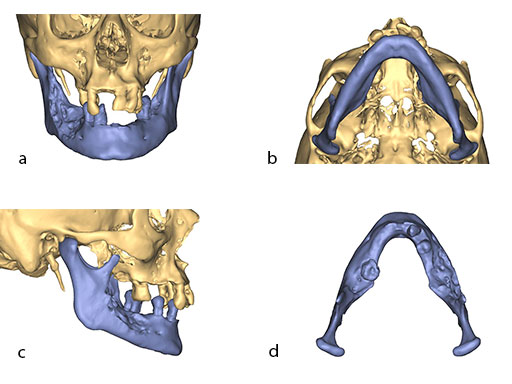

Virtual surgical planning using preoperative CT DICOM datasets of the defective CMF region, and the donor region from where the bone flap will be harvested, provides a detailed outline of the bony framework (eg, an autogenous neomandibular section consisting of an array of fibular segments).

The design of the bony segments and the overall framework is defined in an interactive planning session between the surgeon and a medical engineer. In oncologic surgery, a primary reconstruction is preceded by a virtual tumor resection for exact matching of the defect and the bony restoration. In secondary reconstruction, it will often be necessary to reposition collapsed bony remnants and to level their cut edges in order to define the real extent of the preexisting defect. Patient specific plates for the mandible have the versatility to bridge almost all defect patterns in the mandible (Fig 1abc). After exarticulation of a condyle, they are even compatible with the Matrix Mandible condylar head add-ons as a joint component for temporary replacement. The cutting guides, templates, and the patient specific mandibular reconstruction plates can be supplemented with stereolithographic (STL) models of the mandible, displaying the defect and the composed fibular segments as either a hybrid or as separate items. In the separate format, the models are an ideal instrument for double-checking. The defect size and the correct placement of the patient specific plates for the mandible are controlled by inserting the STL fibular segment assembly in situ. On a side table, the fitting of the real fibular segments into the defect of the STL model can be assessed.

A 58-year-old male patient had oral cancer (T4n0m0) infiltrating the alveolar process and the anterior border of the ascending ramus (Fig 2). The treatment plan involved resection, bilateral neck dissection (levels I to III), and primary mandibular reconstruction with a right osteomyofasciocutaneous fibula flap.